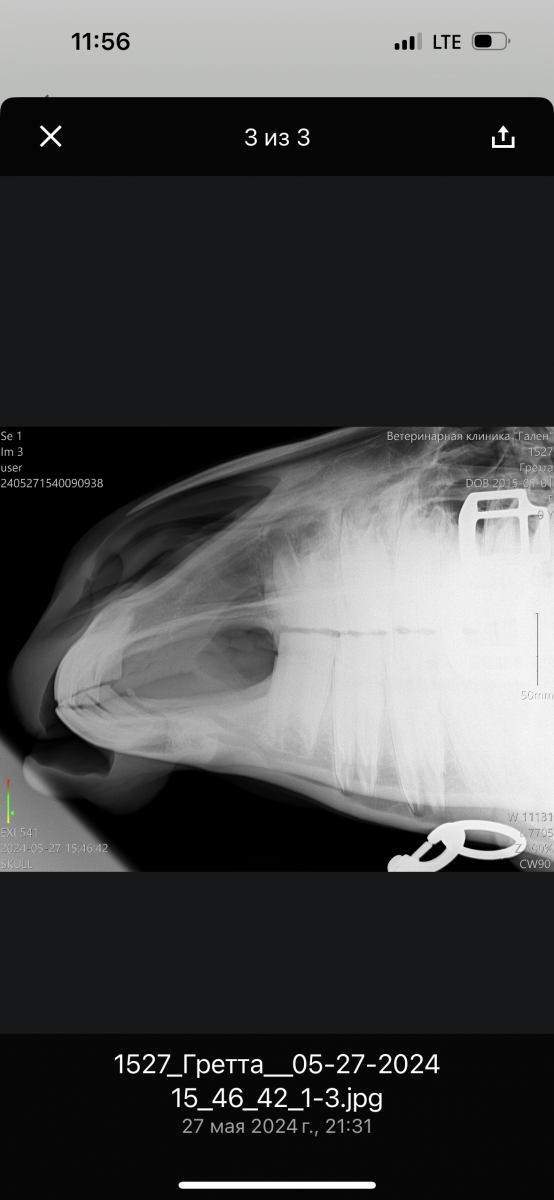

Далее сделали рентген (прилагаю его), врач заподозрил может киста, во рту ничего не нашли (думали на зуб), корни зубов хорошие, десна все тоже.